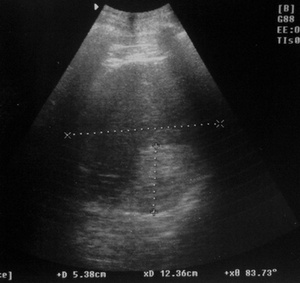

Но.... был у нас тут недавно случай: мужчина 58л, жалобы на боли в левом подреберье, из анамнеза Рак p.Fateri T2N0M0 IIст, IIIкл.гр., после ПДР.

Из протокола УЗИ: в воротах селезенки виз-ся жидкостное образование разм.... инкапсулированное, неоднородной структуры с вероятными признаками абсцедирования.Закл: По УЗ-признакам нельзя исключить абсцесс в воротах селезенки.

19062012656_cr.jpg

19062012656_cr.jpg (44.96 КБ) 1226 просмотров

Операция: Абсцесс селезенки...

Поэтому и в представленном С.В. случае можно предположить абсцесс :?